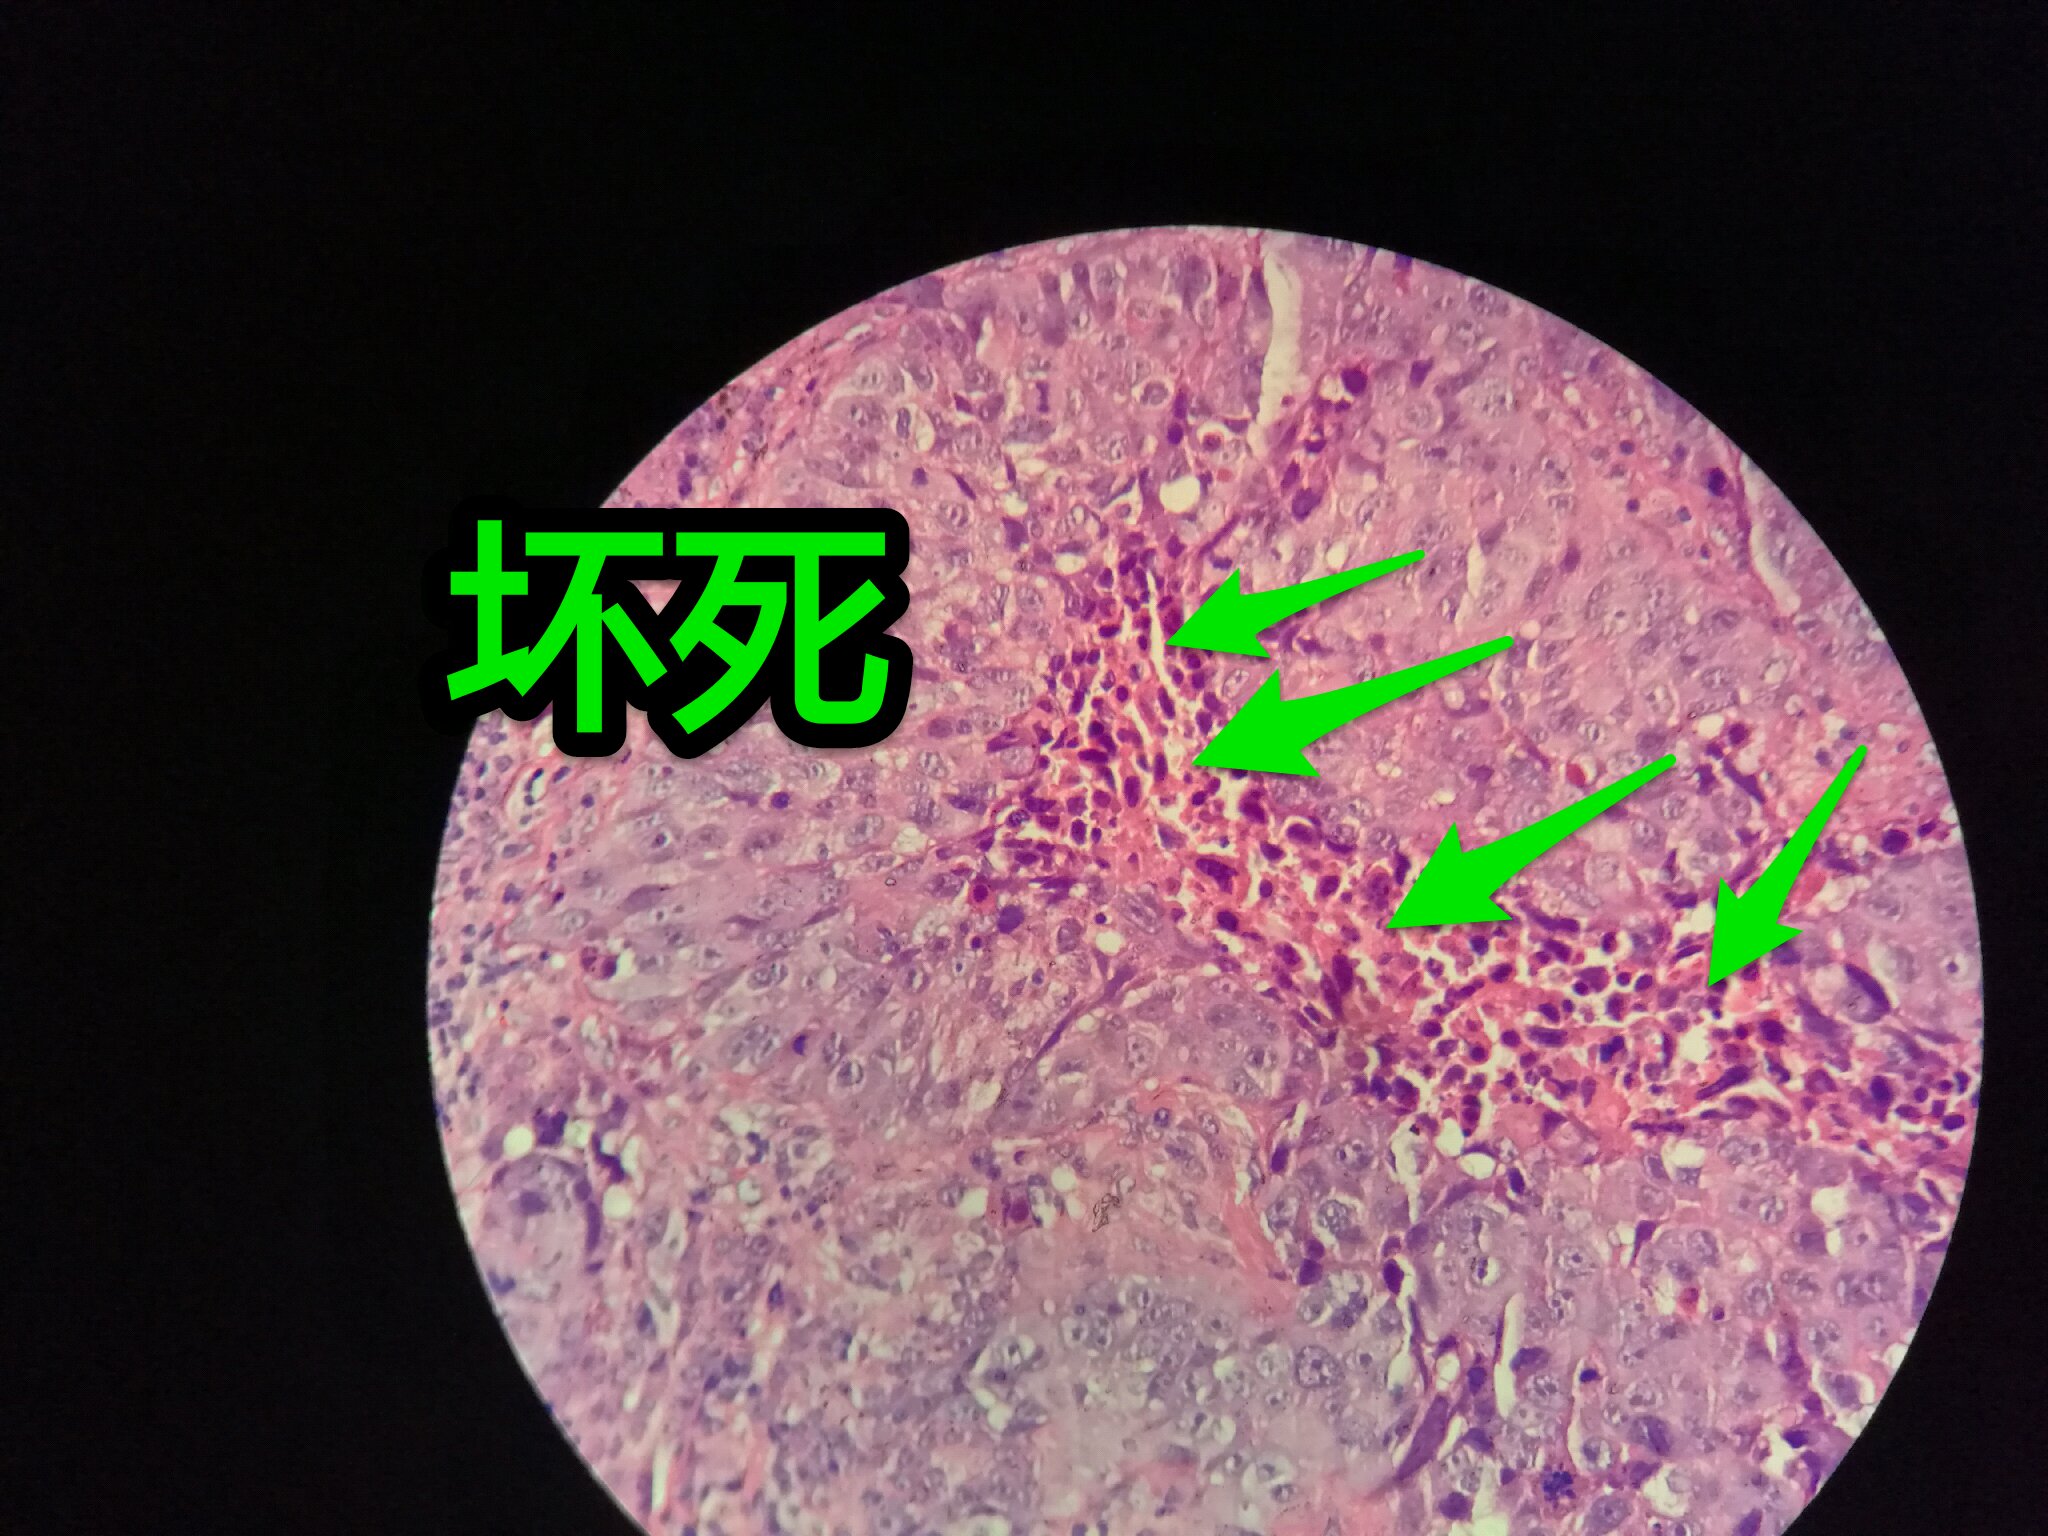

巢团可以很大,中央血供不足,就会坏死

中央红色的,有碎核

这个鳞癌不是早期

坏死也可以很大

较大的粉红区都是坏死,可以看出坏死是因为巢团大,中央坏死

下图是放大